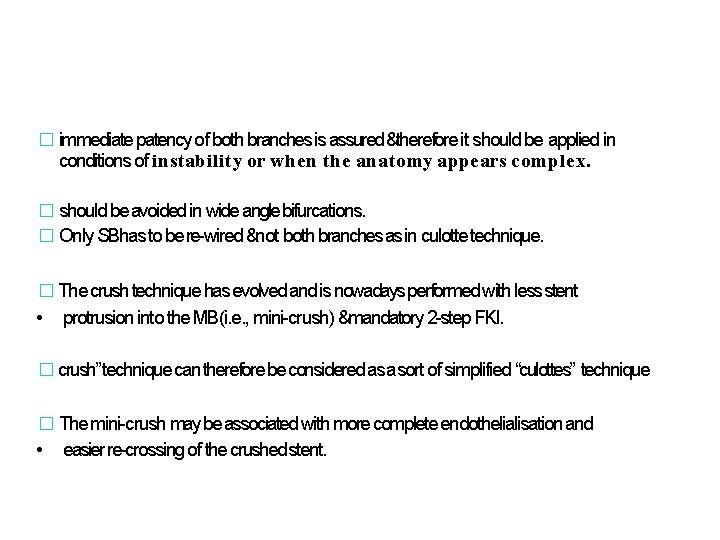

� immediate patency of both branches is assured &therefore it should be applied in conditions of instability or when the anatomy appears complex. � should be avoided in wide angle bifurcations. � Only SBhas to be re-wired ¬ both branches as in culotte technique. � The crush technique has evolved and is nowadays performed with less stent • protrusion into the MB(i. e. , mini-crush) &mandatory 2 -step FKI. � crush” technique can therefore be considered as a sort of simplified “culottes” technique � The mini-crush may be associated with more complete endothelialisation and • easier re-crossing of the crushed stent.